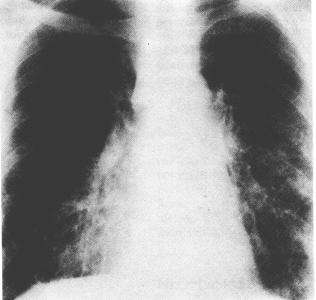

Figura 26-10. Tuberculose. Radiografia do tórax em PA demonstrando adenopatia paratraqueal direita e um infiltrado reticulonodular disfuso de fino a médio. Este é o padrão encontrado em pacientes com estágios finais da infecção pelo HIV e tuberculose. Uma vez que a adenopatia não estão associada com PCP esta não deve ser considerada uma causa provável de doença neste paciente.